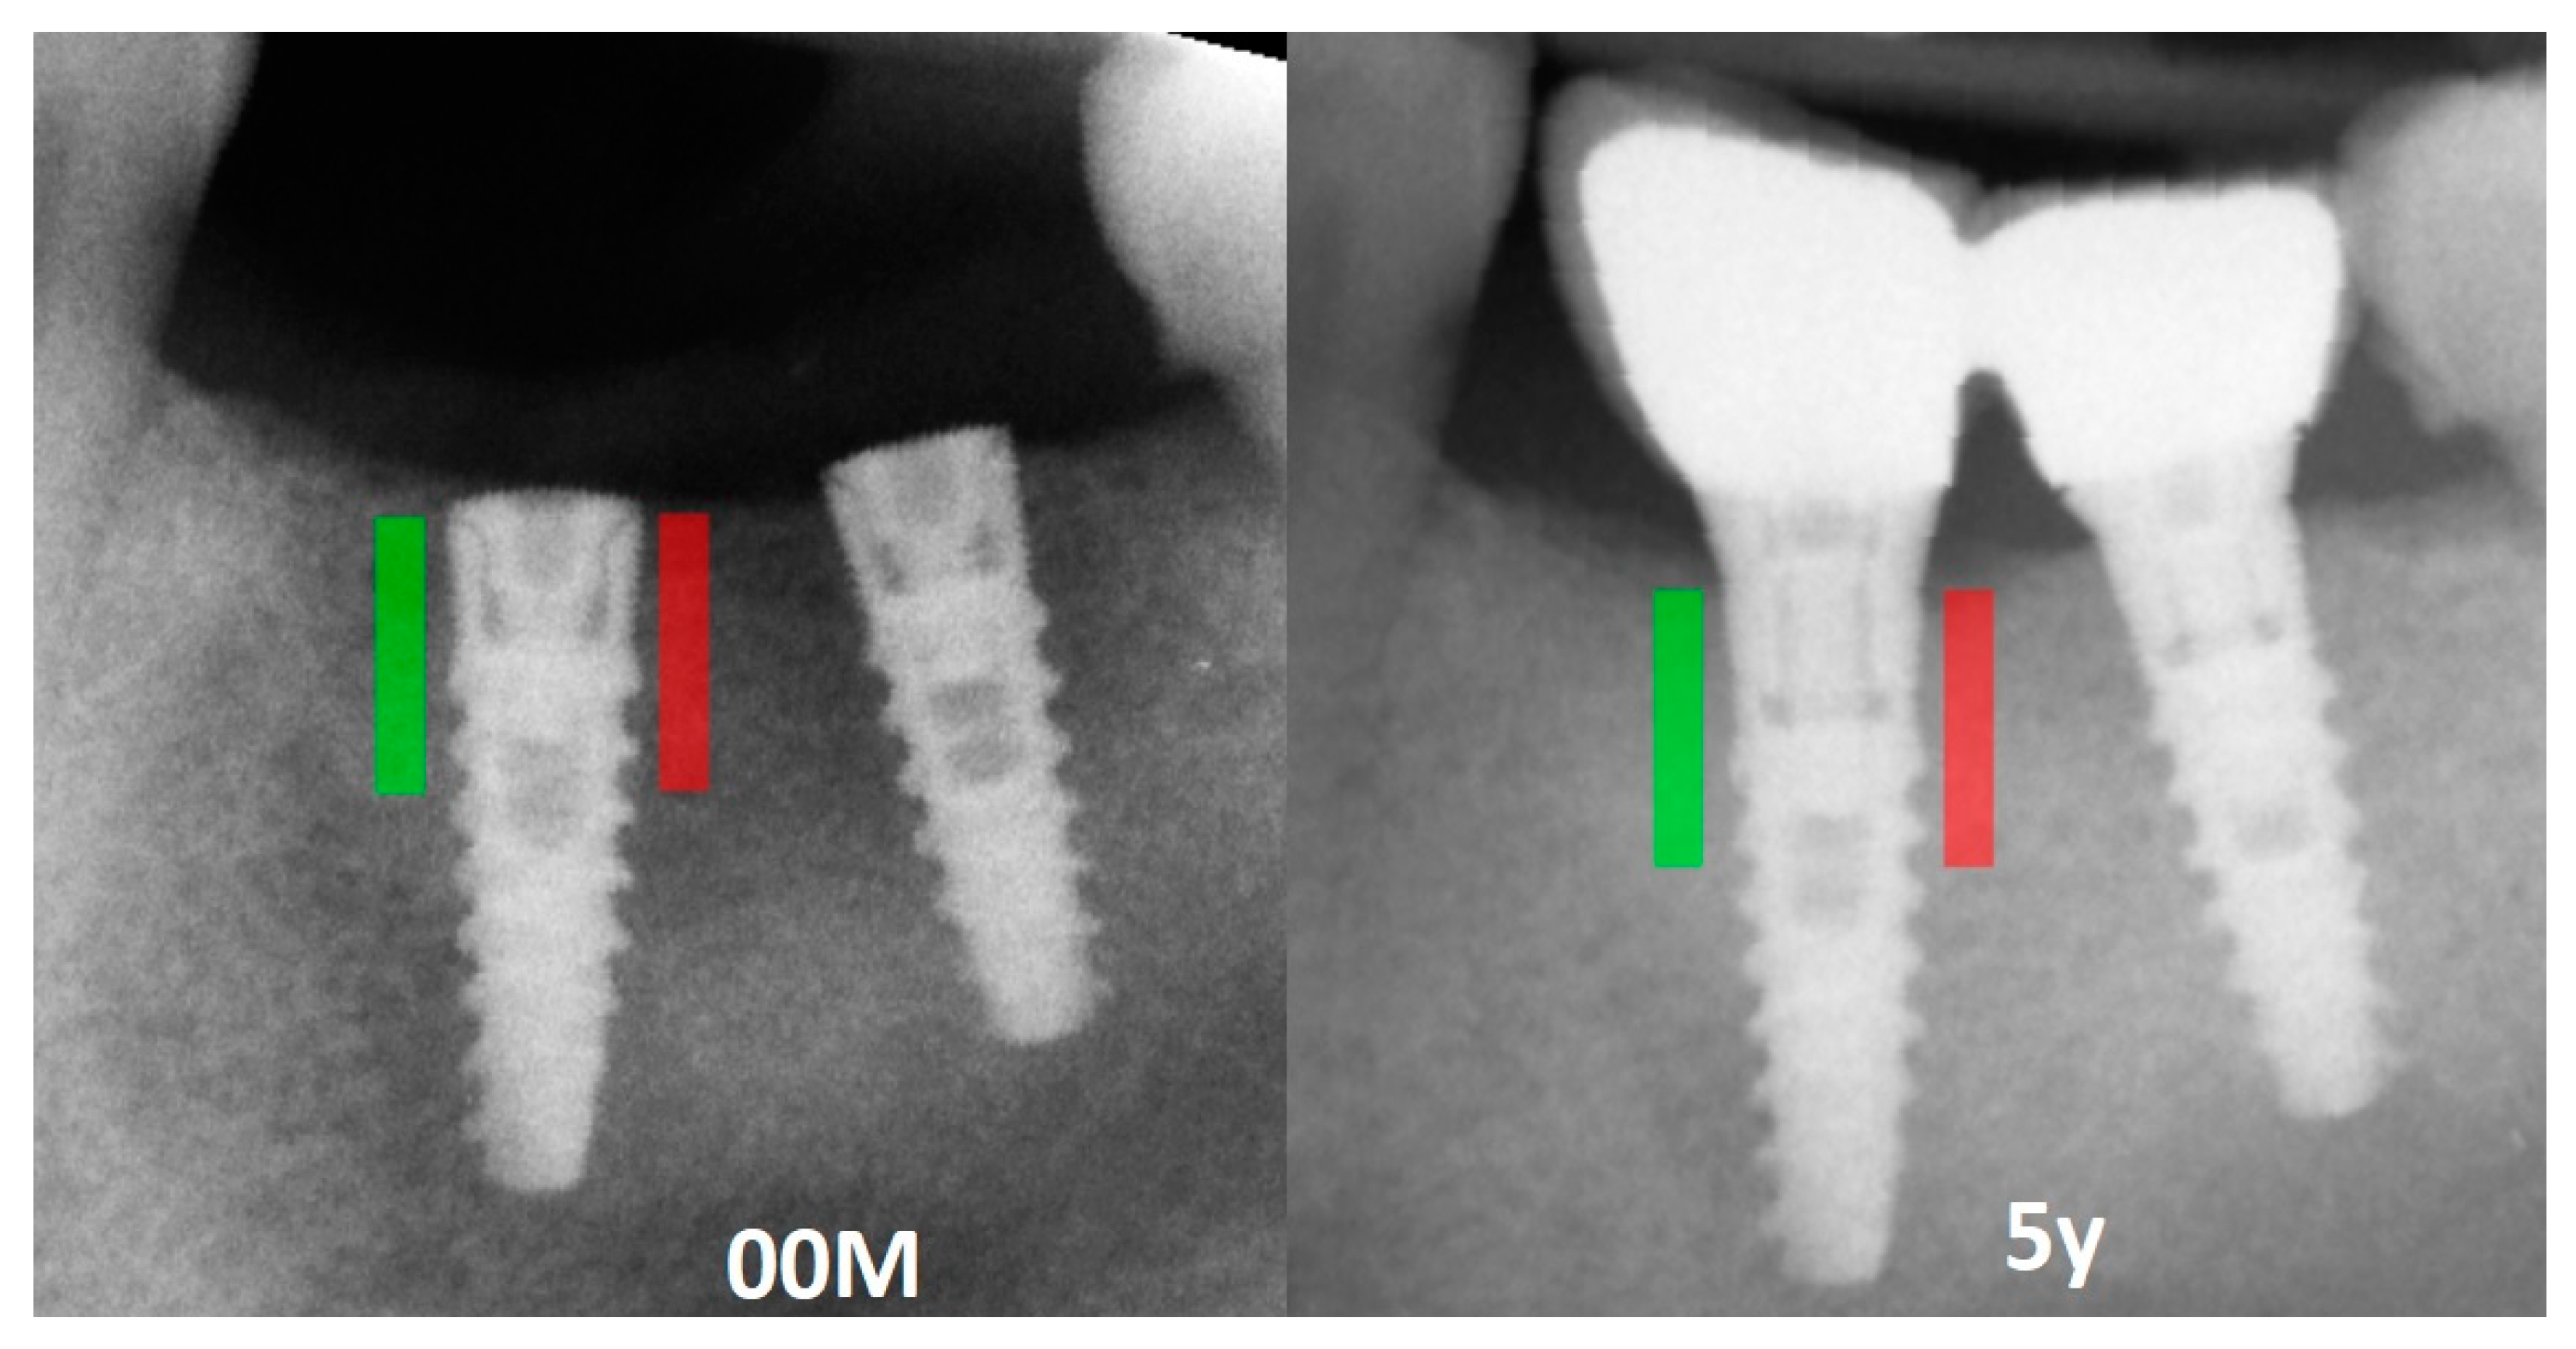

2. Materials and Methods

- Kozakiewicz, M.; Wach, T. Exploring the Importance of Corticalization Occurring in Alveolar Bone Surrounding a Dental Implant. J. Clin. Med. 2022, 11, 7189. [Google Scholar] [CrossRef]

- Kozakiewicz, M.; Skorupska, M.; Wach, T. What Does Bone Corticalization around Dental Implants Mean in Light of Ten Years of Follow-Up? J. Clin. Med. 2022, 11, 3545. [Google Scholar] [CrossRef] [PubMed]

- Kozakiewicz, M. Measures of Corticalization. J. Clin. Med. 2022, 11, 5463. [Google Scholar] [CrossRef]

- Wach, T.; Skorupska, M.; Trybek, G. Are Torque-Induced Bone Texture Alterations Related to Early Marginal Jawbone Loss? J. Clin. Med. 2022, 11, 6158. [Google Scholar] [CrossRef]